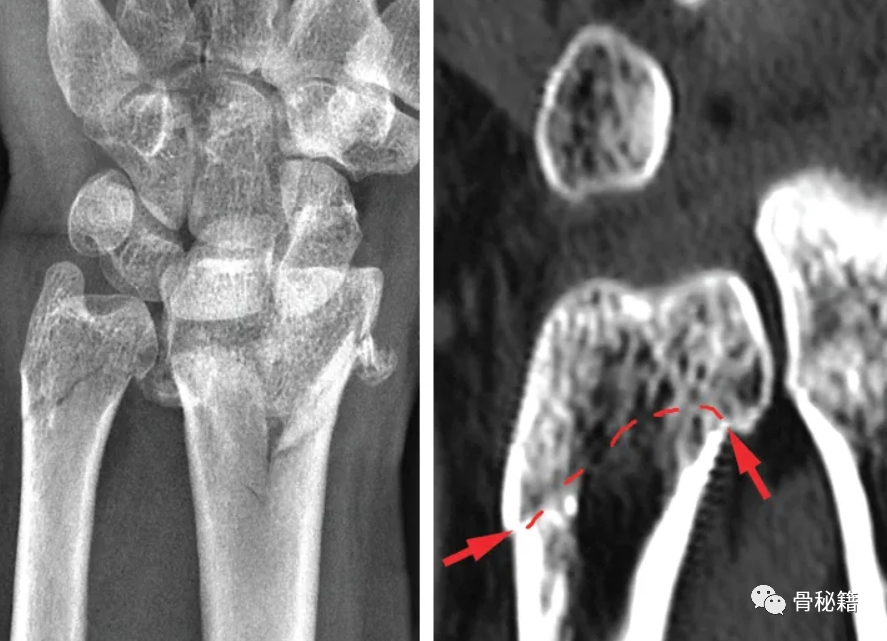

it was impossible to have shortening of the radius of more than 2 mm or 20 degrees of dorsiflexion without complete detachment of the TFCC from the fovea or the sigmoid notch.

曾经有学者研究,如果桡骨短缩2mm或成角20度,那么TFCC就可能有损伤,损伤的类型有多种多样。其中,红色损伤比绿、黄色损伤更容易造成尺骨远端不稳定,所以红色损伤时需要考虑手术治疗,尤其年轻患者。